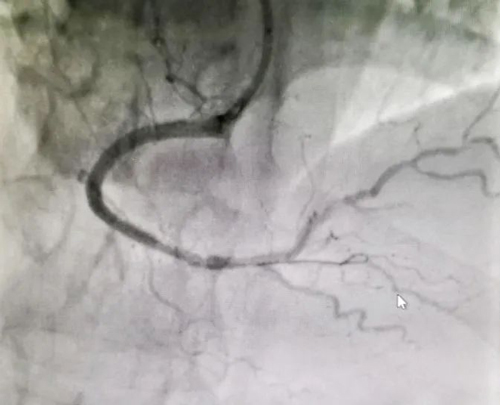

我院胸痛中心手術(shù)團隊嫻熟緊密地配合,在10分鐘內(nèi)成功于右冠遠(yuǎn)段植入1枚支架,讓病變殘余狹窄消失,冠脈血流恢復(fù)正常,患者生命體征平穩(wěn),送回病房進一步診治。

鄭州陽城醫(yī)院胸痛中心在春節(jié)假期連續(xù)兩天成功救治兩名急性心;颊